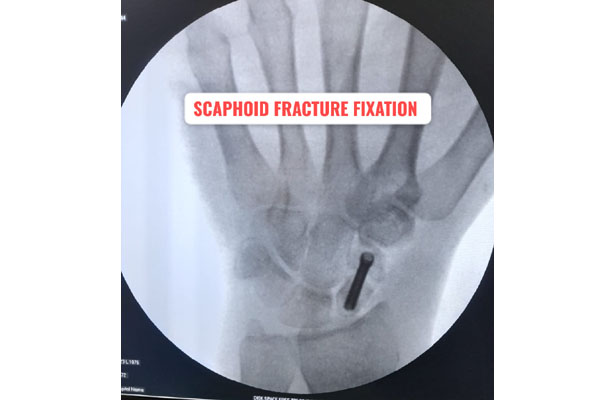

Fracture of bones is commonly handled by almost all orthopaedic surgeons in India. But dealing with comminuted intra-articular fractures (involving joints) is a night mare for most of them. It requires special expertise and experience to deal with such kind fractures. It can involve pelvic acetabular fracture, upper portion of thigh bone ( hip), lower portion of thigh bone ( femur), upper portion of arm bone (humerus head), lower portion of arm bone (humerus), lower portion of forarm bone (lower end of radius) fracture of heel bone, etc. The idea is to maintain the joint (articular) integrity and prevent the permanent loss of movements at that joint. It requires image intensifier (c-arm) to do these surgeries. May be artificial bone or autograft (patient’s own bone taken from iliac bone) to fill in the bone defect/ loss if present. The fracture may take 2- 3 months to heal. Patient may require prolonged physiotherapy to gain near normal range of motion exercises.